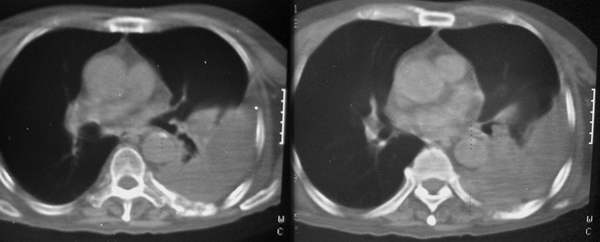

在2006年6月10日ct3798的病例中,我让老师会诊一个病人的肋骨,现在有结果了。病人复查后,发现t8、9椎体已经破坏,并累积椎管。考虑还象个转移,可始终未发现原发灶。有兴趣的可以在提一下见解。

在短短的一个月的时间,胸椎变化这么大,如果说不是恶性,那骨质疏松不会这么快吧!(原来的资料因t8、9没变化,所以没有显示)。请注意我现在发的帖子是以t8、9椎体为住的。

骨破坏,考虑转移